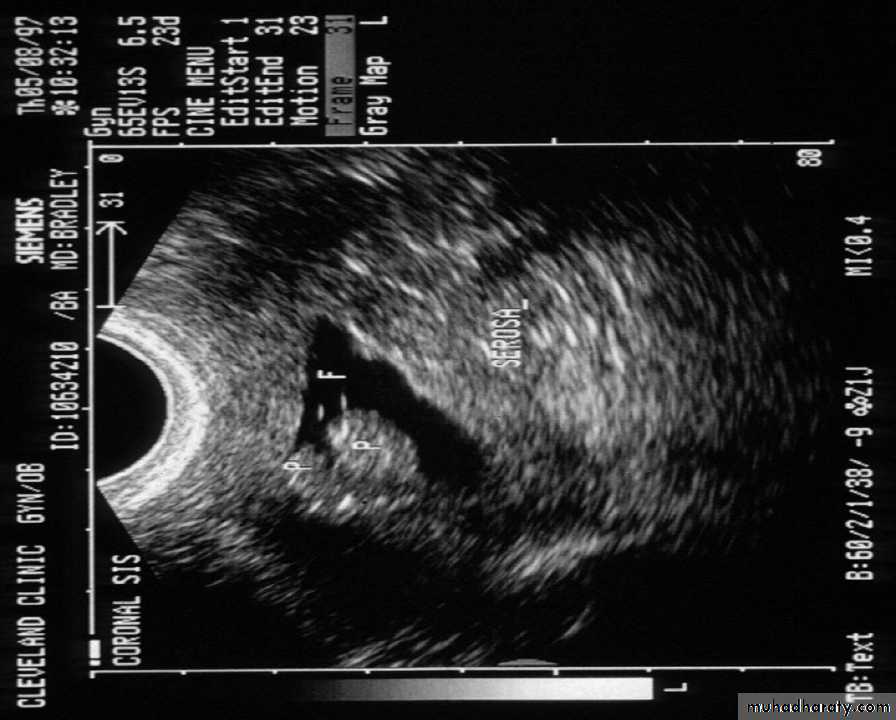

A refinement of vaginal probe ultrasound is saline infusion sonography (SIS). A salt water (saline) solution is injected into the uterus with a small tube (catheter) before the vaginal probe is inserted. The presence of liquid in the uterus helps make any structural abnormalities more distinct. These two non-invasive procedures cause less discomfort than endometrial biopsies and D & Cs, but D & C still remains the definitive test for diagnosing uterine cancer.TVUS